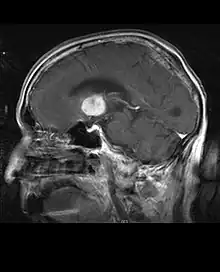

A tomografia computadorizada (TC) e a ressonância magnética (RM) podem detectar efetivamente uma neoplasia no cérebro. A RM é mais sensível que a TC para identificar lesões, mas contraindicações para pacientes com marcapasso cardíaco, próteses incompatíveis, clipes metálicos e outros. A TC continua sendo o método de escolha para detectar calcificações dentro de lesões ou erosões ósseas da calota craniana ou da base. A utilização de agentes de contraste, que são iodados no caso da TC e paramagnéticos ( gadolínio ) no caso da RM, permite a aquisição de informações sobre a vascularização e integridade da barreira hematoencefálica, uma melhor definição do tumor tumoral comparado ao edema circundante e à geração de hipóteses sobre o grau de malignidade . O exame radiológico também permite avaliar os efeitos mecânicos e consequentes alterações nas estruturas cerebrais decorrentes do tumor, como hidrocefalia e hérnias, cujos efeitos podem ser fatais. Finalmente, na preparação para a cirurgia, esse diagnóstico pode ser usado para determinar a localização da lesão ou a infiltração do tumor em áreas vitais do cérebro. Para isso, a RM é mais eficiente que a TC, pois pode fornecer imagens tridimensionais.

As ferramentas de diagnóstico por imagem radiológica destacam a mudança no tecido neoplásico em comparação com o parênquima cerebral normal (através de alterações na densidade do tecido fotografado eletronicamente na TC e na intensidade do sinal na RM). Como a maioria dos tecidos patológicos, os tumores também são reconhecidos por um acúmulo aumentado de água intracelular. Na tomografia computadorizada aparecem hipodensa, ou seja, de menor densidade que o parênquima cerebral, na tomografia de ressonância magnética nuclear com relaxamento spin-lattice T 1 hipointenso e em relaxamento spin-spin T 2 bem como a ponderação de prótons (PD) hiperintensa.

A área saudável do cérebro não deve mostrar nenhuma luminescência específica em uma imagem radiológica. Portanto, nem é preciso dizer que é dada atenção a faixas de sinal de contraste maiores.

No tecido tumoral, em geral, a maior proporção de realce pelo contraste se deve à barreira hemato-tumor particular que permite a passagem de iodo (TC) e gadolínio (RM) para o espaço intersticial extravascular intratumoral. Isso aumenta o sinal (densidade ou intensidade) do tumor. No entanto, deve-se ter cuidado para garantir que o realce do contraste não diferencie definitivamente a neoplasia do edema periferida. De fato, o achado anátomo-patológico no tecido tumoral de glioma infiltrante maligno, como no glioblastoma e no astrocitoma anaplásico, também mostra além do edema vasogênico causado pela destruição da barreira hematoencefálica pelo tumor. Esta última condição clínica é pouco detectável pelo diagnóstico por imagem.

A tomografia computadorizada do cérebro normalmente mostra uma massa de tecido que pode ser realçada por qualquer contraste. Na TC, os gliomas de baixo grau geralmente parecem isodensos ao parênquima normal e, portanto, podem não apresentar realce pelo contraste. Da mesma forma, lesões na fossa posterior do crânio são difíceis de identificar na TC. Consequentemente, os resultados dessa tomografia isoladamente nem sempre são suficientes para fins diagnósticos. Em casos duvidosos, o uso da ressonância magnética mais sensível é essencial.

Na ressonância magnética, um tumor intracraniano aparece como uma lesão maciça que pode se tornar mais luminescente após o uso do agente de contraste. No entanto, há sempre uma anomalia de sinal na ressonância magnética, que indica a presença de neoplasia ou edema vasogênico. Normalmente, o aumento da luminescência (realce pelo contraste) é indicativo de um tumor de grau mais alto de malignidade. Um anel contrastante é característico do glioblastoma, com a porção luminescente correspondendo à parte vital do tumor maligno e a área mais escura-hipointense à necrose tecidual.